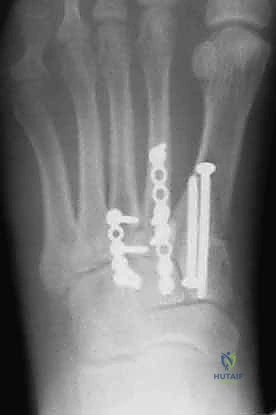

1. الرد المفتوح والتثبيت الداخلي (ORIF - Open Reduction and Internal Fixation)

هذا هو الإجراء الكلاسيكي والأكثر شيوعاً. يهدف إلى إعادة العظام إلى مكانها الطبيعي (الرد) وتثبيتها باستخدام معدات طبية (مسامير، شرائح، أو أسلاك) حتى تلتئم الأربطة والعظام.

خطوات العملية:

4. التثبيت (Fixation): يتم تثبيت العظام باستخدام مسامير معدنية خاصة (Solid or Cannulated Screws) تعبر المفاصل لتثبيتها بإحكام. في بعض الحالات، يتم استخدام شرائح معدنية صغيرة للحفاظ على الاستقرار.

5. مسمار ليزفرانك: الخطوة الأهم هي وضع "مسمار ليزفرانك" (Lisfranc Screw) الذي يمر من العظم المسماري الإنسي إلى قاعدة المشط الثاني، لتعويض وظيفة الرباط الممزق.

6. الإغلاق: يتم إغلاق الشقوق الجراحية بعناية تجميلية ووضع القدم في جبيرة لحمايتها.